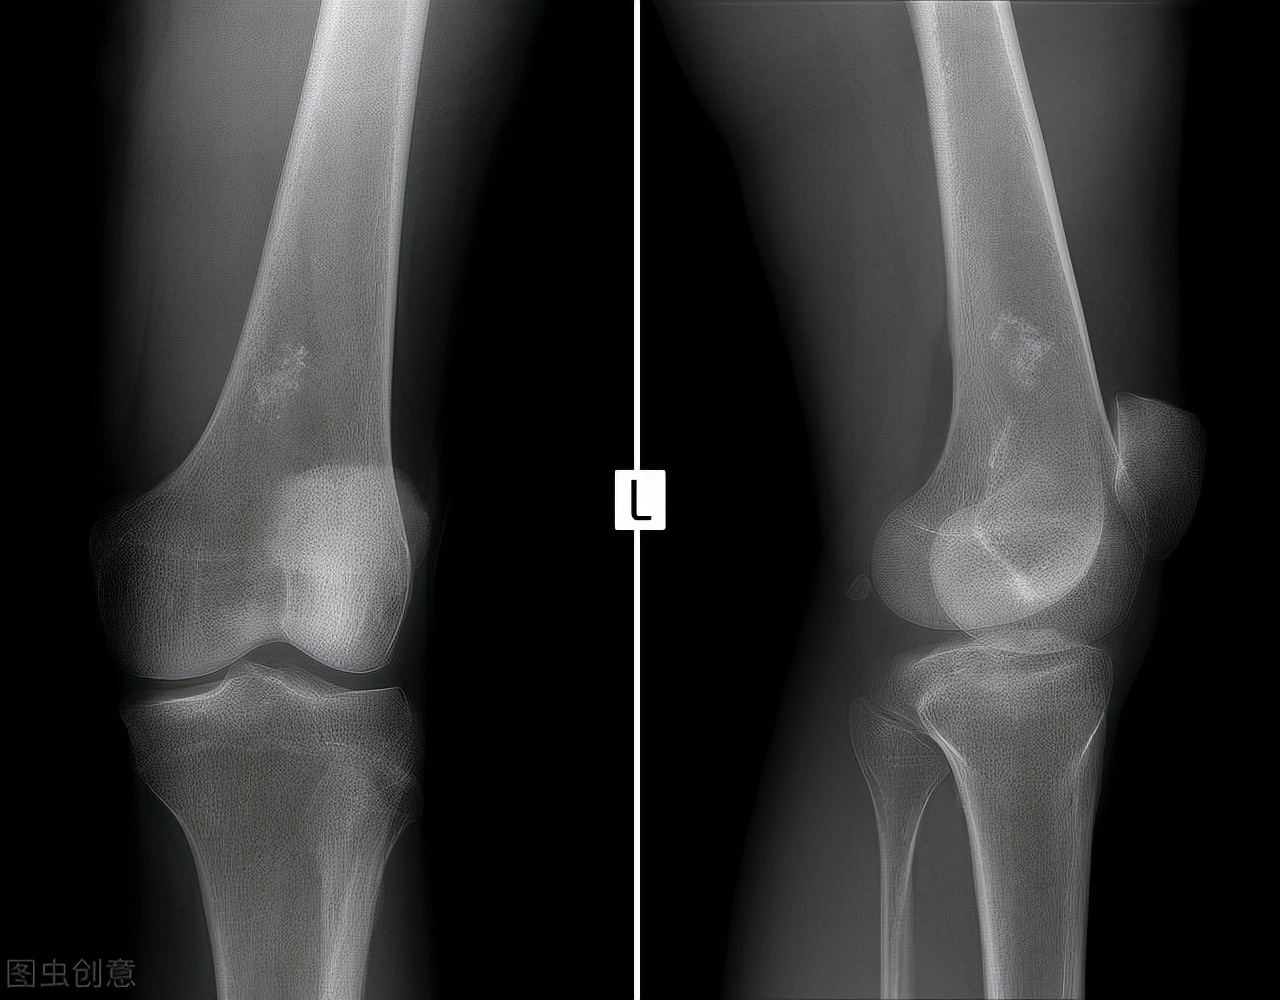

首先,我们看看,老年人群腰背部酸痛最常见的疾病有哪些?发病率最高,目前最常见的要数腰椎间盘突出了,尤其是经常过度弯腰工作的人群,该类人群经常使腰部处于负重的状态,在加上腰椎间盘发生老化,容易使髓核突出,所以发生腰椎间盘突出以后容易腰酸、腰痛。除此之外,因为人体的神经走行在椎管之中,腰椎间盘突出以后,容易挤压椎管之中的神经,患者会同时出现腿部的疼痛,严重时甚至会有手足麻木,有时患者的日常生活也会受到影响,行走时可能会出现跛行。那么,除了腰椎间盘突出以外,那些人群还以出现腰酸、腰痛呢?工作时的不良体位、劳动姿势、搬运重物等引起的慢性累积性损伤,遇到潮湿寒冷等物理刺激后极容易发生腰酸、腰痛。转到腰椎间盘突出这个问题,感觉自己腰酸、背痛、手足麻木时,怎么确定自己得了这个病呢?去相应的骨科门诊或脊柱外科门诊,医生给你通过查体,开(MRI),就可以确定是不是了。

核磁共振(MRI)

腰椎间盘